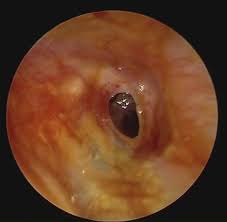

Otitis Media Chronic Suppurative Ear Nose And Throat Disorders Msd Manual Consumer Version

Otitis Media Chronic Suppurative Ear Nose And Throat Disorders Msd Manual Consumer Version from www.msdmanuals.com

Chronic suppurative otitis media (csom) is a stage of ear disease in which there is chronic infection of the middle ear and mastoid, and in which a central perforation of the tympanic membrane (or a patent tympanostomy tube) and discharge (otorrhea) are present. Successful topical therapy consists of 3 important components: Like csom, ome often occurs after acute otitis media (aom) … Chronic suppurative otitis media is characterized by a persistent drainage from the middle ear through a perforated tympanic membrane (tm). Chronic bacterial infection of the middle ear with persistent purulent discharge through a perforated tympanic membrane. Chronic suppurative otitis media is a serious disease with a bacterial infection in the middle ear. Chronic suppurative otitis media (csom) is one of the leading causes of preventable disabling hearing impairment (dhi) in developing countries. Chronic suppurative otitis media (csom) involves a cycle of inflammation, ulceration, granulation and infection in the middle ear. It is characterized by chronic drainage from the middle ear associated with tympanic membrane (tm. Synonyms include chronic otitis media, chronic mastoiditis, and chronic tympanomastoiditis. The condition is often seen in patients with a history of acute otitis media with tm rupture and presents with painless otorrhea and conductive hearing loss. Chronic suppurative otitis media 1. Acute otitis media and blockage of a eustachian tube are among the causes of chronic suppurative otitis media.